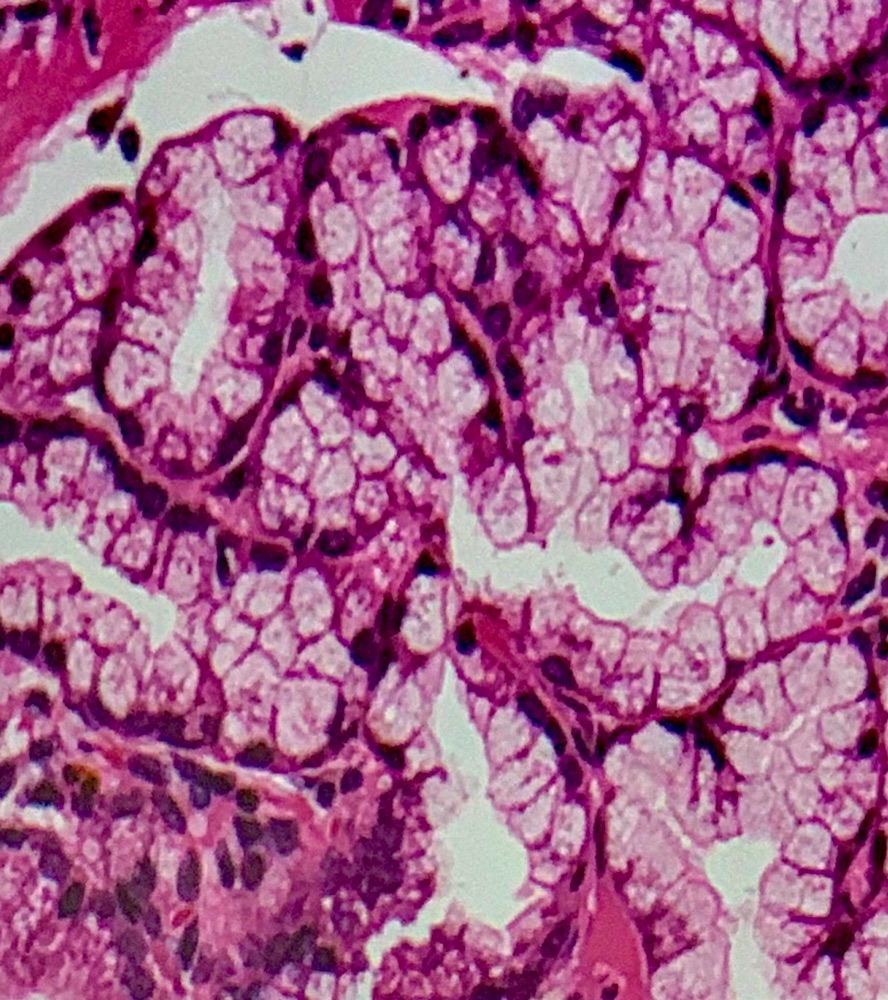

1 Tissue ประเภทใด

5 จากภาพเป็นเนื้อเยื่อชนิดใด

6 จงบอกชนิดของเนื้อเยื่อ

12 จากภาพคือ เนื้อเยื่อชนิดใด

13 จากภาพ คือเนื้อเยื่อใด

14 เนื้อเยื่อชนิดใด